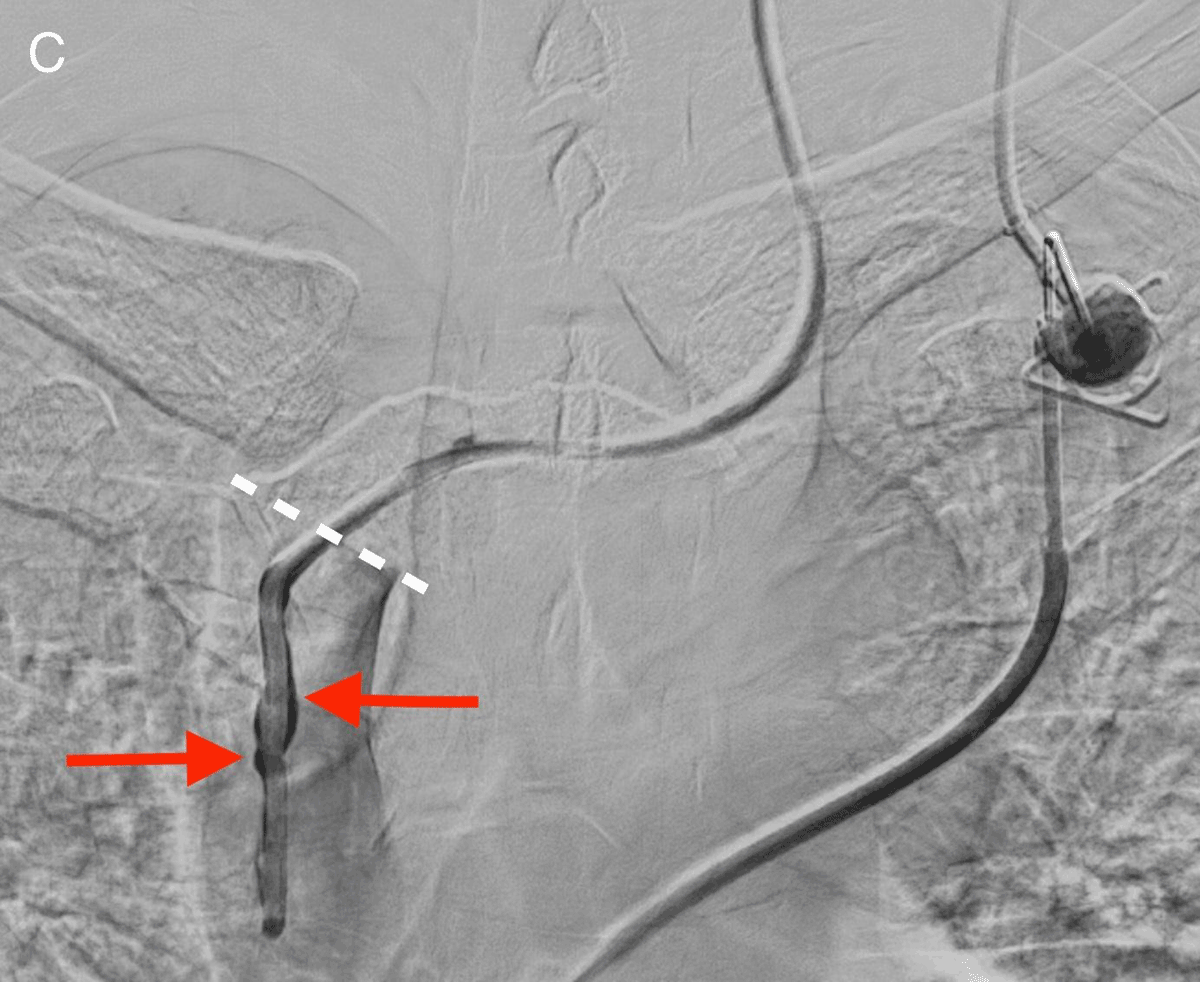

After re-assessment of the initial chest radiograph, a C-arm cone-beam computed tomography was ordered and demonstrated the incorrect anterior positioning of the last centimeters of the catheter, presumably in the right internal thoracic vein (arrow Figure B). Opacification by iodine contrast injection through the CVP showed thrombosis around the tip of the catheter with backflow to the brachiocephalic vein before antegrade flow (arrows, Figure C, the white dotted line shows the catheter through ostium of the right internal thoracic vein). Via femoral vein access, we created a loop around the CVP catheter in the left brachiocephalic vein with a guidewire and a snare, allowing for removal of the catheter by traction from the internal thoracic vein.

Figure C